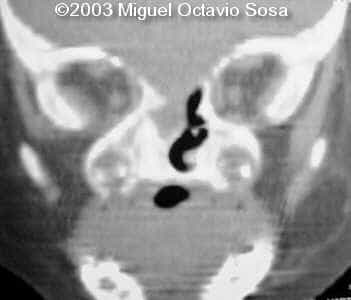

A female newborn was delivered at 38 week, by cesarean section due to breech presentation. Size of right eye is bigger than left, and there is total absence of the right nostril. Apgar 9 at birth. No complications during postpartum. Newborn is actually under study by plastic surgeon.

These are the 3D CT reconstruction.